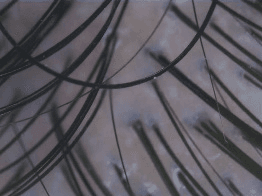

| Clear | ![]() | ![]() | ![]() | ![]() |

| Almost Clear | ![]() | ![]() | ![]() | ![]() |

| Moderate | ![]() | ![]() | ![]() | ![]() |

| Poor | ![]() | ![]() | ![]() | ![]() |

| Severe | ![]() | ![]() | ![]() | ![]() |